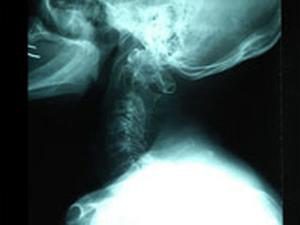

ゆう整骨院では、交通事故による怪我・むち打ち(ムチウチ)の治療が保険で受けられ安心です。(自賠責保険対応)